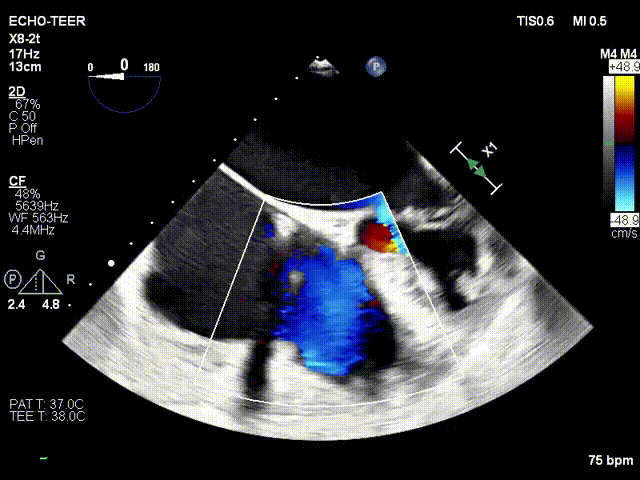

术前超声

术后超声